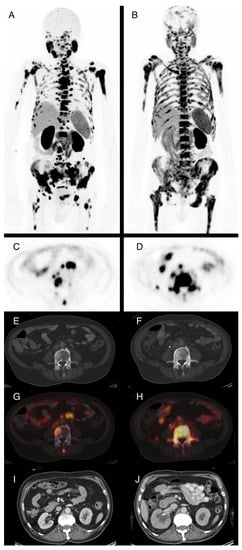

3.3. PSMA-PET/CT Response